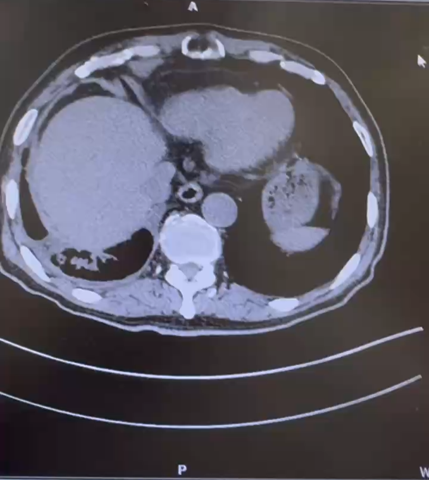

CT(2022.1):1. 左肾肿块,肾癌并出血可能;2. 左输尿管上段结石并周围炎症,左肾结石并积水;3. 右肾萎缩;4. 肝囊肿。

治疗后复查 CT(2022.7):左肾透明细胞 CA 治疗后改变,肿块较前缩小,强化程度减低,左侧副肾动脉可见;余况同前。

CT( 2024.4.26 ):1. 左肾 NSS 术后改变,左肾新见多发结节状等密度灶,考虑复发;2. 右输尿管上段结石消失,右肾积水缓解,右肾萎缩;3. 余况同前。